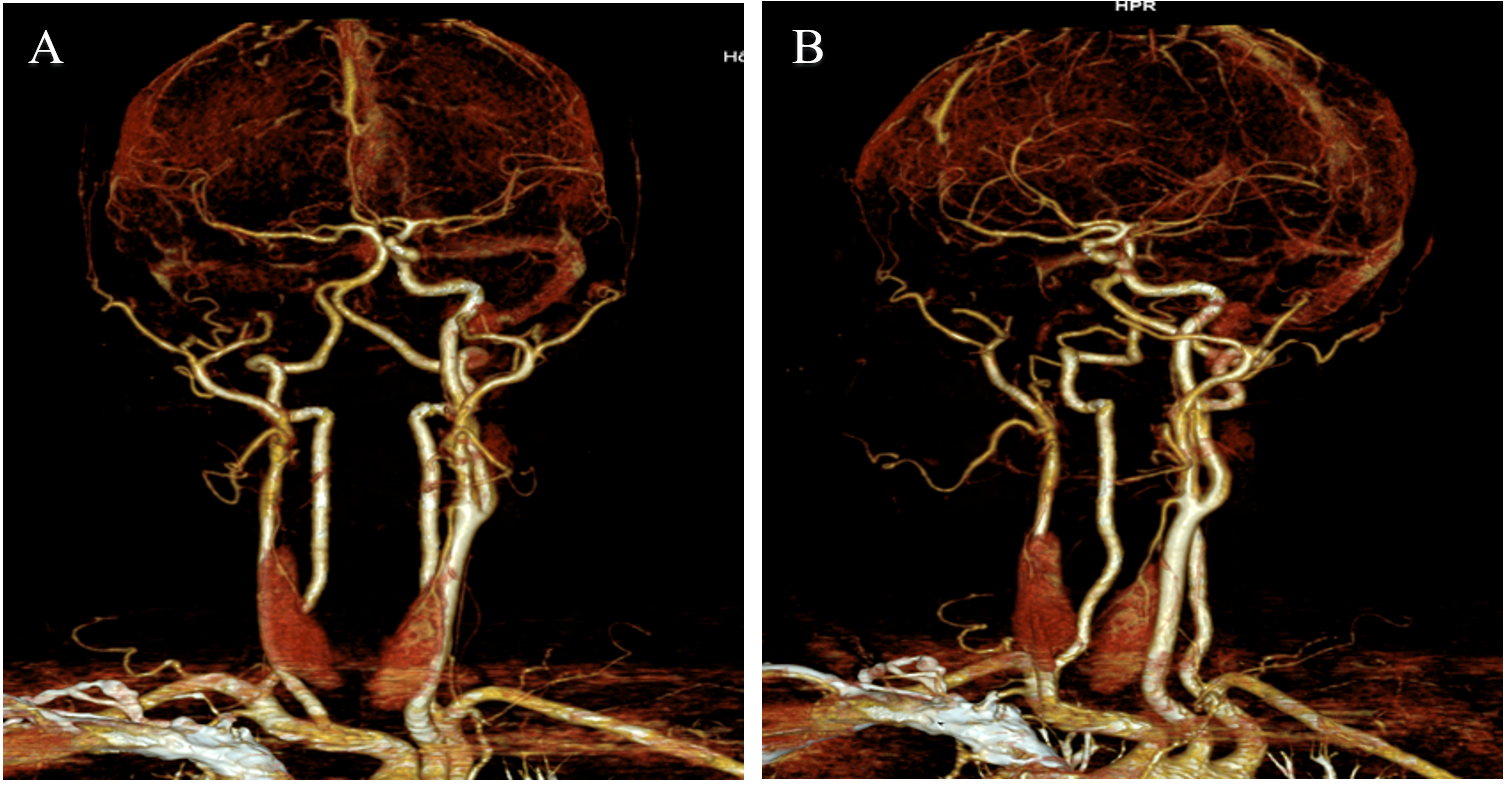

The CT angiography showed that the right internal carotid artery was not visible from its origin to the cerebral vessels, as well as compensatory dilation of the collateral vessels, provided by the anterior and posterior communicating arteries, which appeared tortuous, dilatation of the contralateral carotid artery, and dilatation of the right hemispheric cortical veins.

The right external carotid artery arises from the right common carotid artery, with no identifiable internal carotid artery.

Figure 3: Right external carotid artery arises from the right common carotid artery, with no identifiable internal carotid artery.

Figure 4: Angio-CT showing the absence of the right internal carotid artery.